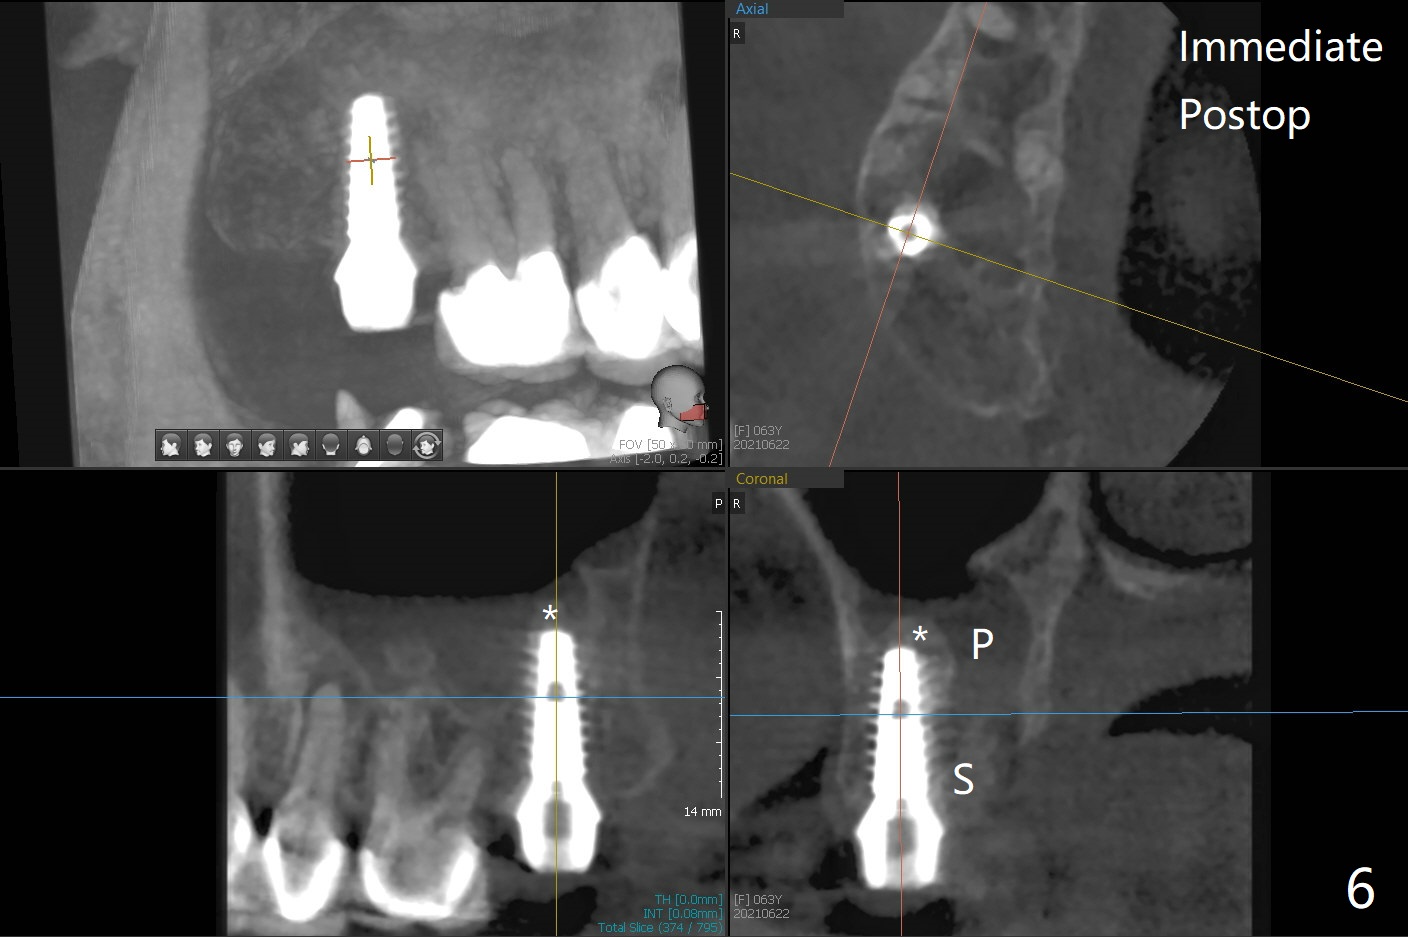

When the tooth #2 is extracted, there is sinus perforation in the palatal apex, consistent with preop CT (Fig.1: P). There is no bone shaving associated with drill sequence in the buccal socket (until 3.5x8.5 mm). With sticky bone and 4.5x10 mm IS dummy implant, sinus lift does not happen. Sinus floor perforation is felt when a 2.2x10 mm drill is used slowly. But air leaks from the palatal socket. With bone graft, a 4x10 mm dummy implant lifts the sinus (Fig.2). After further graft and 4.5x10 mm dummy implant, a 5x11 mm final implant is placed with 15 Ncm with sinus lift (Fig.3,4 *). Following abutment insertion, sticky bone is packed around the implant and abutment (Fig.5,6 S). Prior to final implant placement, a small piece of PRF and collagen and Osteogen Plugs are placed in the palatal socket for repair. Before discharge, there is mild nasal hemorrhage.